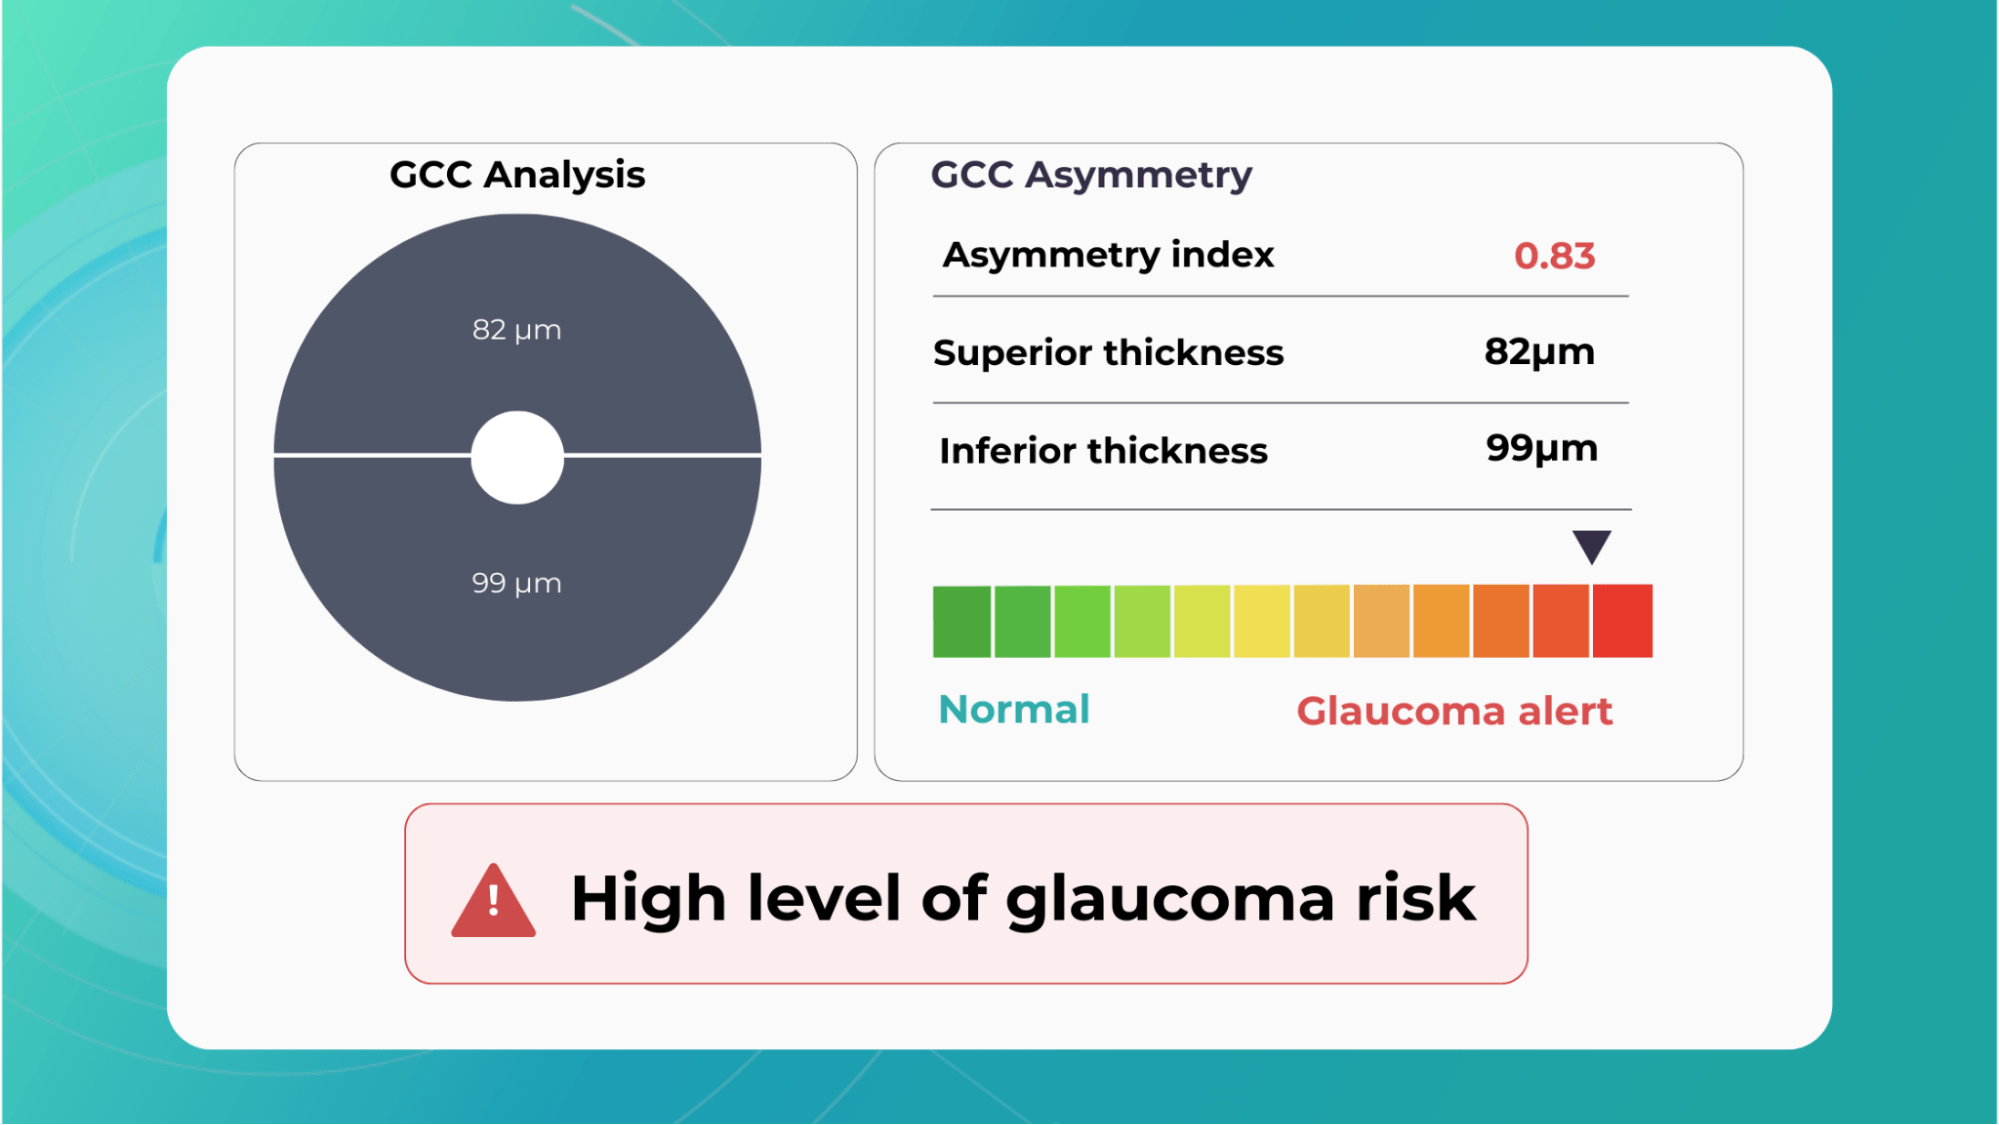

For instance, AI today can assess the early risk of glaucoma based on the GCC asymmetry measurements. Here is how AI-powered OCT workflow would look.

Another significant benefit of AI systems lies in their approach to OCT analysis for glaucoma. Traditional methods rely on normative databases to assess retinal normality, but these databases are often limited in size and represent a select group of individuals. This can result in missed diagnoses of early glaucoma in those who deviate from the “norm” or unnecessary referral from optometry to ophthalmology for those who don’t fit the “normal” profile but have healthy eyes. AI can overcome this limitation by providing more personalized and comprehensive analysis.

Millions risk irreversible vision loss due to undiagnosed glaucoma, underscoring the need for improved early detection. Current tests often rely on observing changes over time, delaying treatment assessment and hindering early identification of rapid disease progression. OCT frequently detects microscopic damage to ganglion cells and thinning across these layers before changes are noticeable through other tests. However, the earliest signs on the scan can still be invisible to the human eye.

AI algorithms offer insights into glaucoma detection by routinely analyzing the ganglion cell complex, measuring its thickness, and identifying any thinning or asymmetry to determine a patient’s glaucoma risk without additional clinician effort.

Another significant benefit of AI systems is that OCT for glaucoma usually utilizes a normative database to assess retinal normality. However, these databases are limited in size and represent an average of a select group of people, potentially missing early glaucoma development in those who deviate from the “norm.” Conversely, individuals may be unnecessarily referred for treatment due to not fitting the “normal” profile, even if their eyes are healthy.